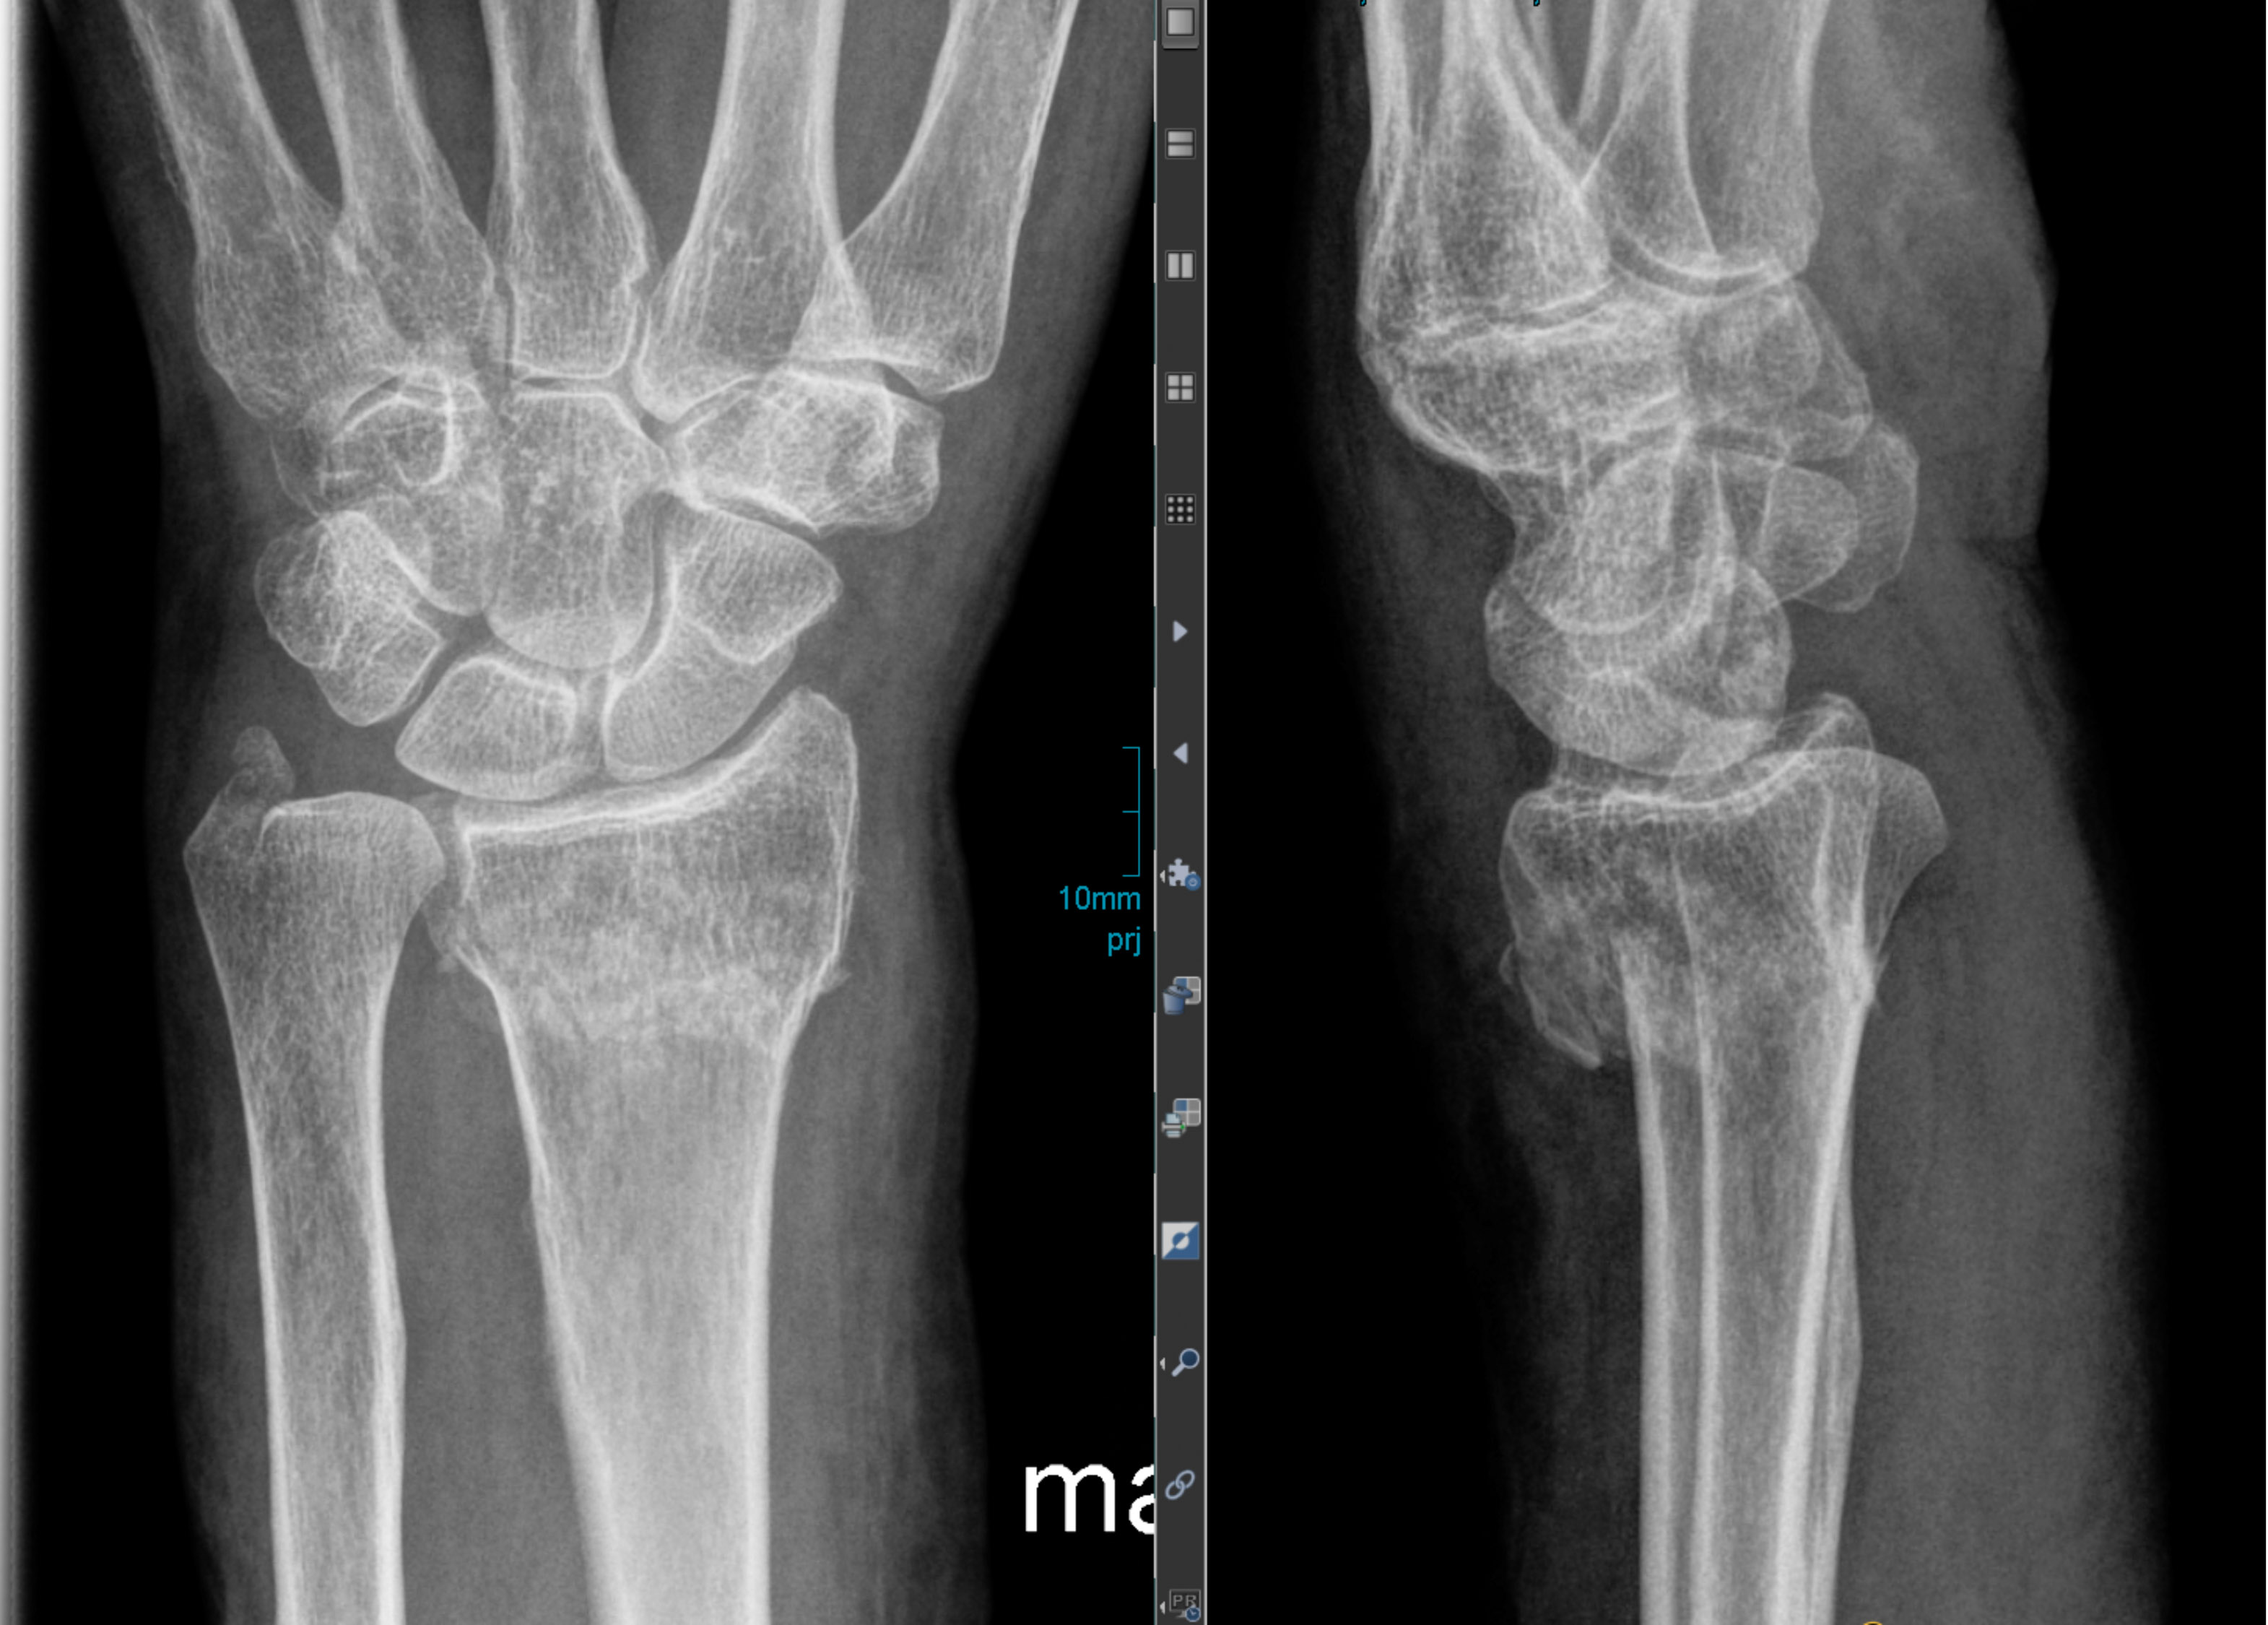

„Bricht sich jemand das Bein, treten kurz danach an der Bruchstelle lokale Immunreaktionen auf. Der Körper sondiert sozusagen die Lage und beseitigt schadhaftes Gewebe. Mit der Zeit überwachsen Knochenzellen den bruchbedingten Spalt und der Bruch heilt ab“, erklärt Professorin Anita Ignatius die normalen Heilungsprozesse. Die Direktorin des Instituts für Unfallchirurgische Forschung und Biomechanik gehört zum Sprecherkreis des Ulmer Trauma-Sonderforschungsbereichs, in dem die molekularen Wechselwirkungen von physischen und psychischen Traumata beforscht werden. Bei langanhaltendem Stress kommt es jedoch zu Störungen dieser akuten immunologischen Prozesse und zu einem Überschießen der Entzündungsreaktion. So entwickeln sich einerseits im Knochenmark vermehrt Immunzellen wie Neutrophile Granulozyten, die an der Bruchstelle in die dort entstandenen Hämatome einwandern. Andererseits ist die Umwandlung von Knorpel zu Knochen und damit die Knochenneubildung gestört, wie sich in der Ulmer Studie zeigte. Die Biegesteifigkeit der Knochen nimmt messbar ab, und das neu gebildete Knochengewebe an der Bruchstelle wird nicht mehr so hart.